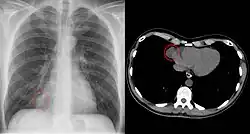

Since pericardial cysts are often asymptomatic, the most common diagnosis is through incidental finding on a chest x-ray.[1][2] Differentiation of pericardial cysts from diverticula is usually impossible as both the lesions have similar radiological appearance. The lone differentiating feature is the presence of communicating tract between pericardium and the cyst cavity in the diverticula, unlike the fully walled off pericardial cyst.[4][5] When patients have symptoms, transthoracic echocardiogram is one of the first tests used to look for a pericardial cyst.[3] CT or MRI may also be used to diagnose pericardial cysts.[4][6][7] On CT and MRI a pericardial cyst will commonly appear as a round, fluid-filled structure surrounded by thin walls.[4][6][7] Diagnosis of a pericardial cyst can also be made before birth using ultrasound.[2]